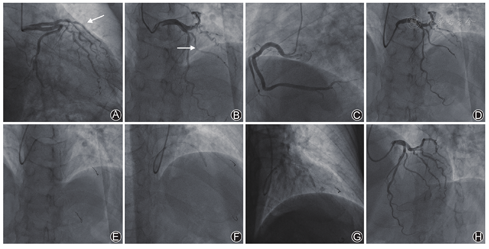

常规消毒铺巾后,穿刺右侧桡动脉,送入5F多功能造影导管,行冠状动脉造影。造影示左主干未见明显狭窄,左前降支近段狭窄40%,中段弥漫性病变,狭窄最重,达80%,累及第一对角支近段,狭窄50%;左回旋支未见明显狭窄,右冠状动脉近段狭窄30%,中段狭窄30%,左心室后支中段狭窄50%,后降支中段狭窄30%(图3)。

选用6 F EBU3.5指引导管,经CorPath GRX辅助系统调整指引导管至左主干开口,分别将0.014 in (1 in=0.025 m)Runthrough及Sion导丝置于CorPath GRX系统不同轨道中,术者在介入操作舱通过操作控制台控制床旁机械臂对驱动盒带内导丝模块进行控制,依次将导丝送入前降支及第一对角支远端,Sion导丝通过对角支开口病变时,利用CorPath GRX系统TechnIQ智能化技术中的"RoR"模式,即将导丝送至对角支开口远处,利用"RoR"模式回退导丝同时旋转角度,从而顺利进入对角支。后续在机器人系统辅助下送入2.5 mm×20 mm半顺应性球囊进行病变预扩张,回撤球囊时利用机器人系统测量病变长度为29.8 mm,进而选用3.0 mm×32 mm药物洗脱支架,利用机械手柄精准移动功能对支架进行定位,以12 atm (1 atm = 101.325 kPa)扩张释放,送入3.25 mm×12 mm非顺应性球囊,以18~20 atm进行后续优化扩张,复查造影提示支架膨胀贴壁良好,对角支近段病变未明显加重,成功回撤全部器械,再次复查冠状动脉造影提示前降支支架植入处未见明显残余狭窄,心肌梗死溶栓治疗(thrombolysis in myocardial infarction,TIMI)血流3级(图3)。手术操作时间为50 min,造影剂用量为60 ml。